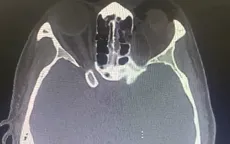

VTV.vn - Khoa Cấp cứu, Bệnh viện Trung ương Quân đội 108 vừa tiếp nhận cấp cứu một bệnh nhân nữ 42 tuổi, bị tràn khí hốc mắt và dưới da vùng mi mắt sau khi xì mũi mạnh.